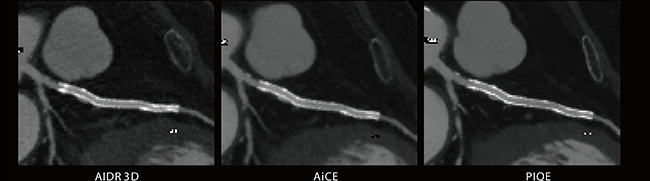

■Aquilion ONE / PRISM Editionの冠動脈CT

AiCEはAIDR 3Dと比較しステント(Ultimaster、3.0×18mm)のブルーミングアーチファクト、ノイズが低減されている。PIQEではさらに低減され、ステント内腔のより正確な診断が期待できる。また、違和感なく大幅なノイズ低減がされていることにより、被ばく低減にも期待できる。